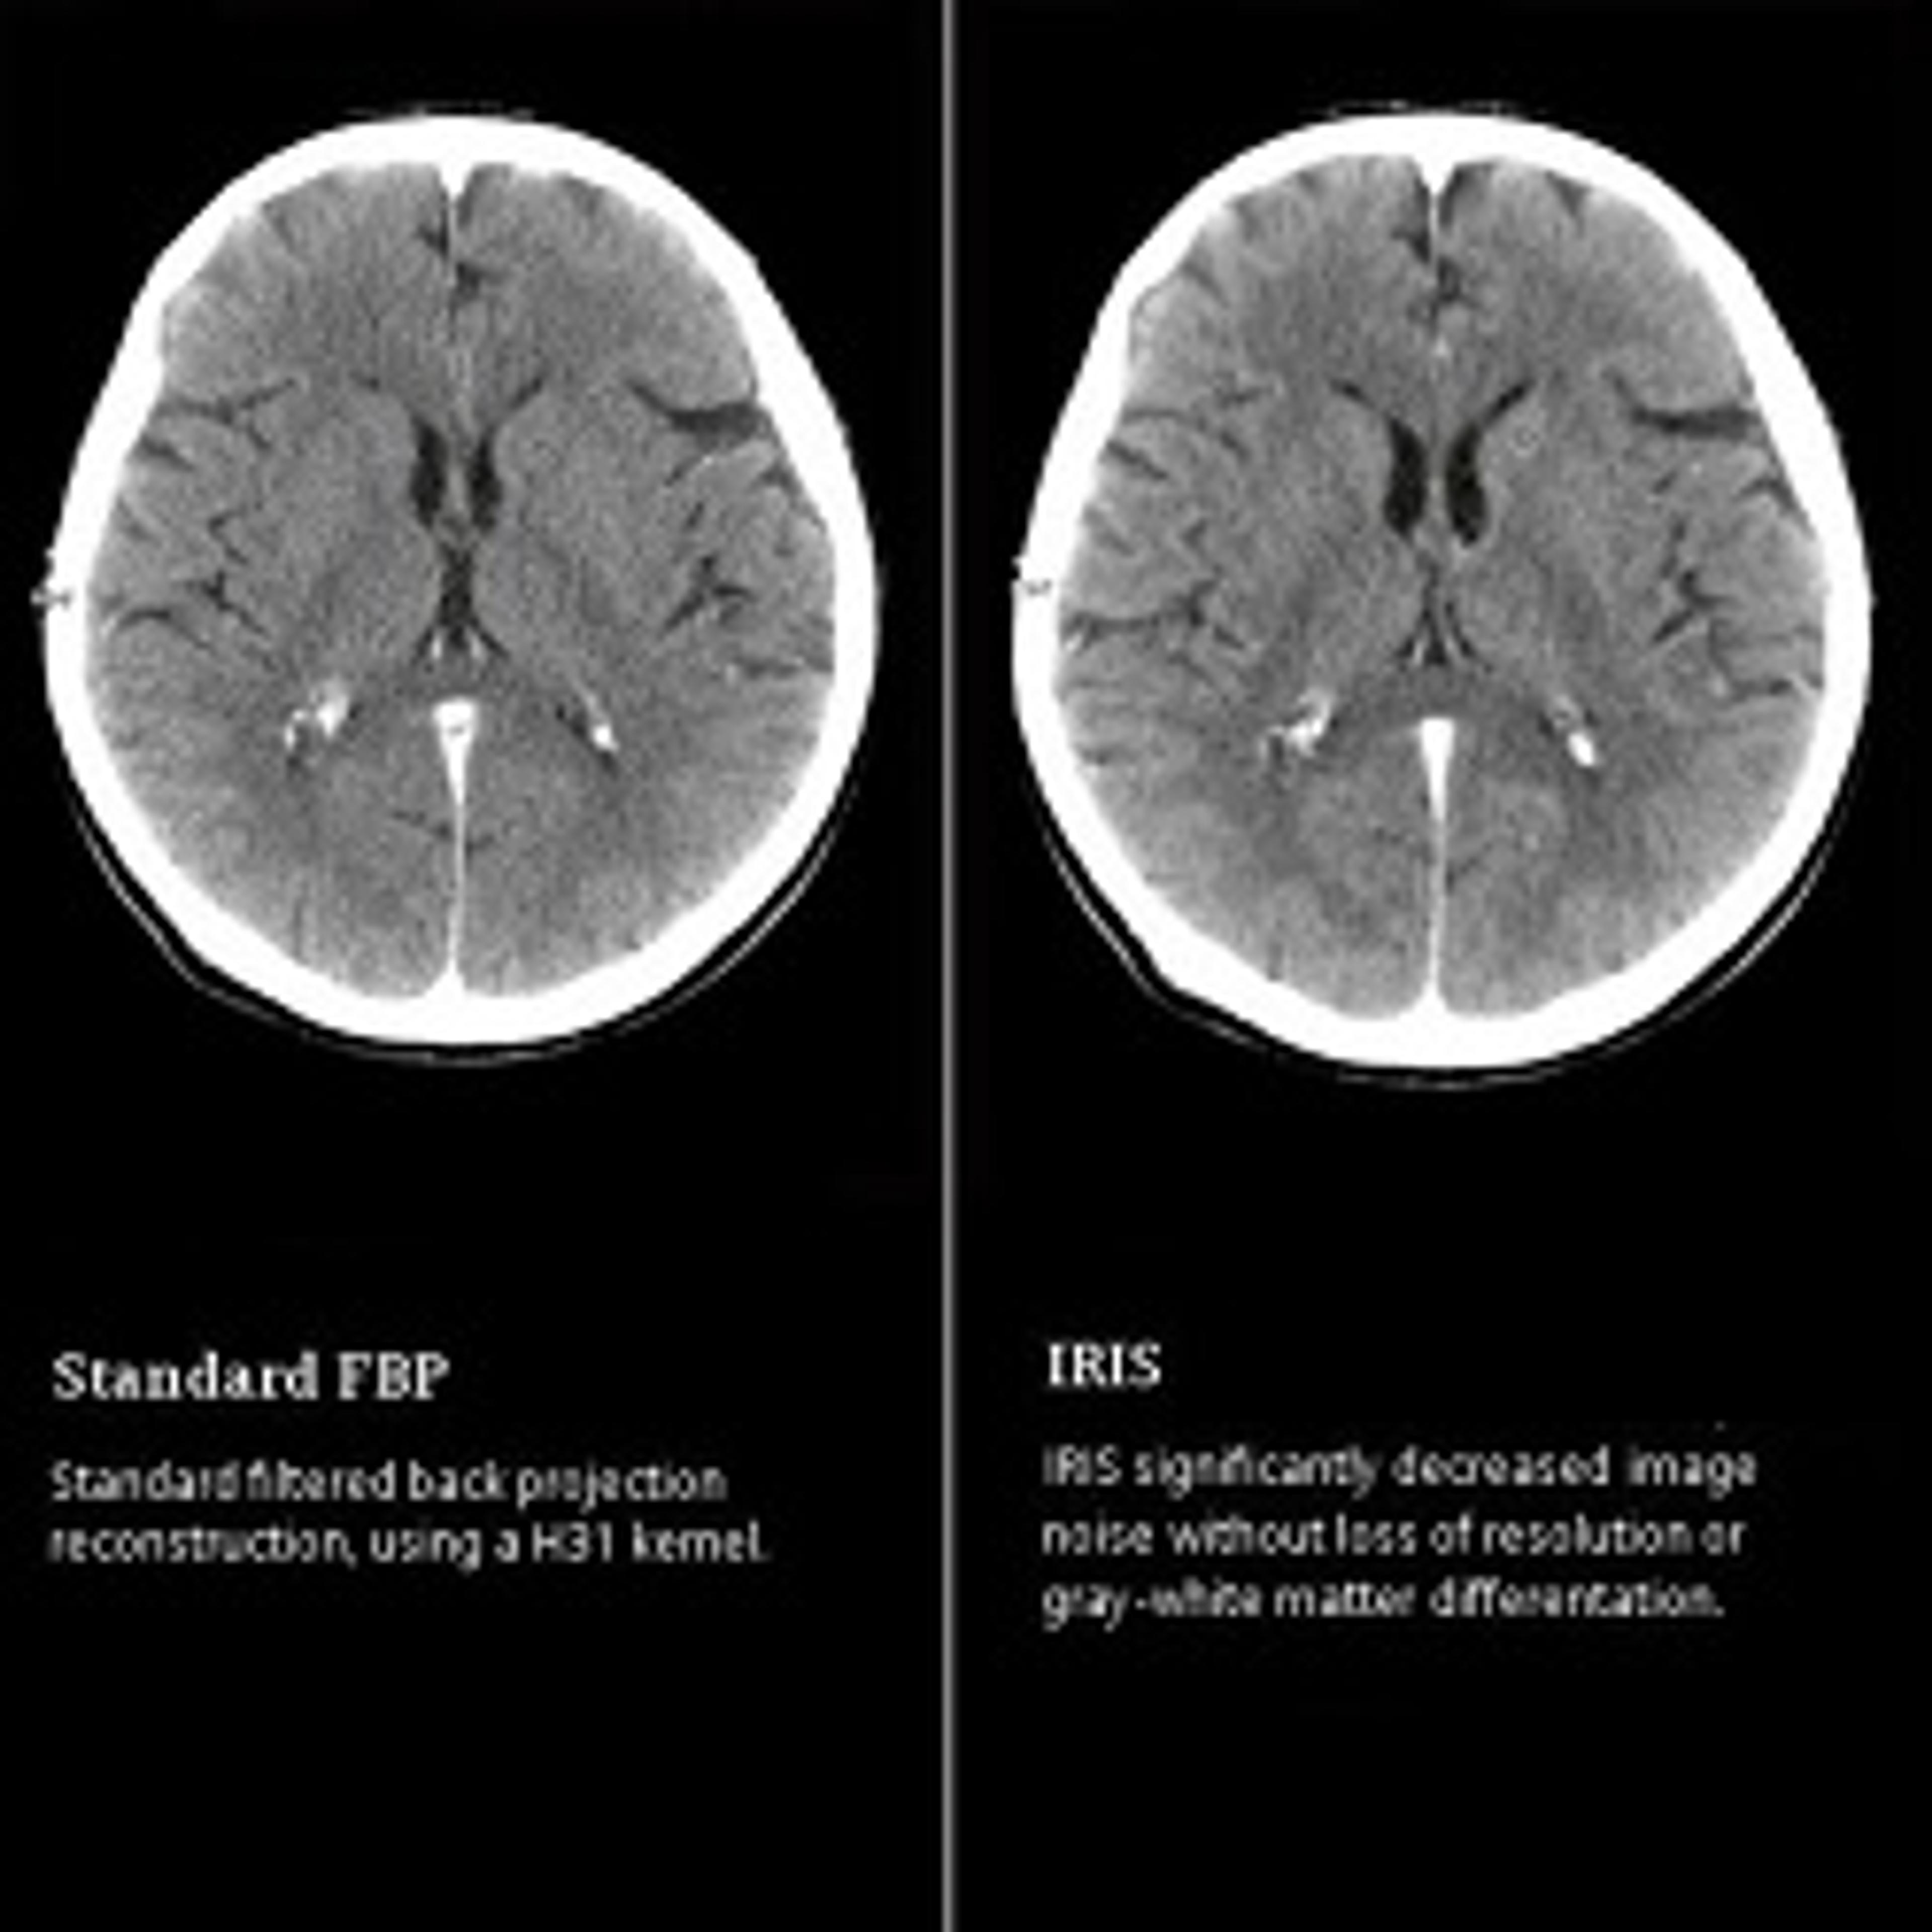

IRIS allows to enhance spatial resolution and to reduce image noise by introducing multiple iteration steps in the reconstruction process, thus enabling dose reduction. Required system : SOMATOM D...